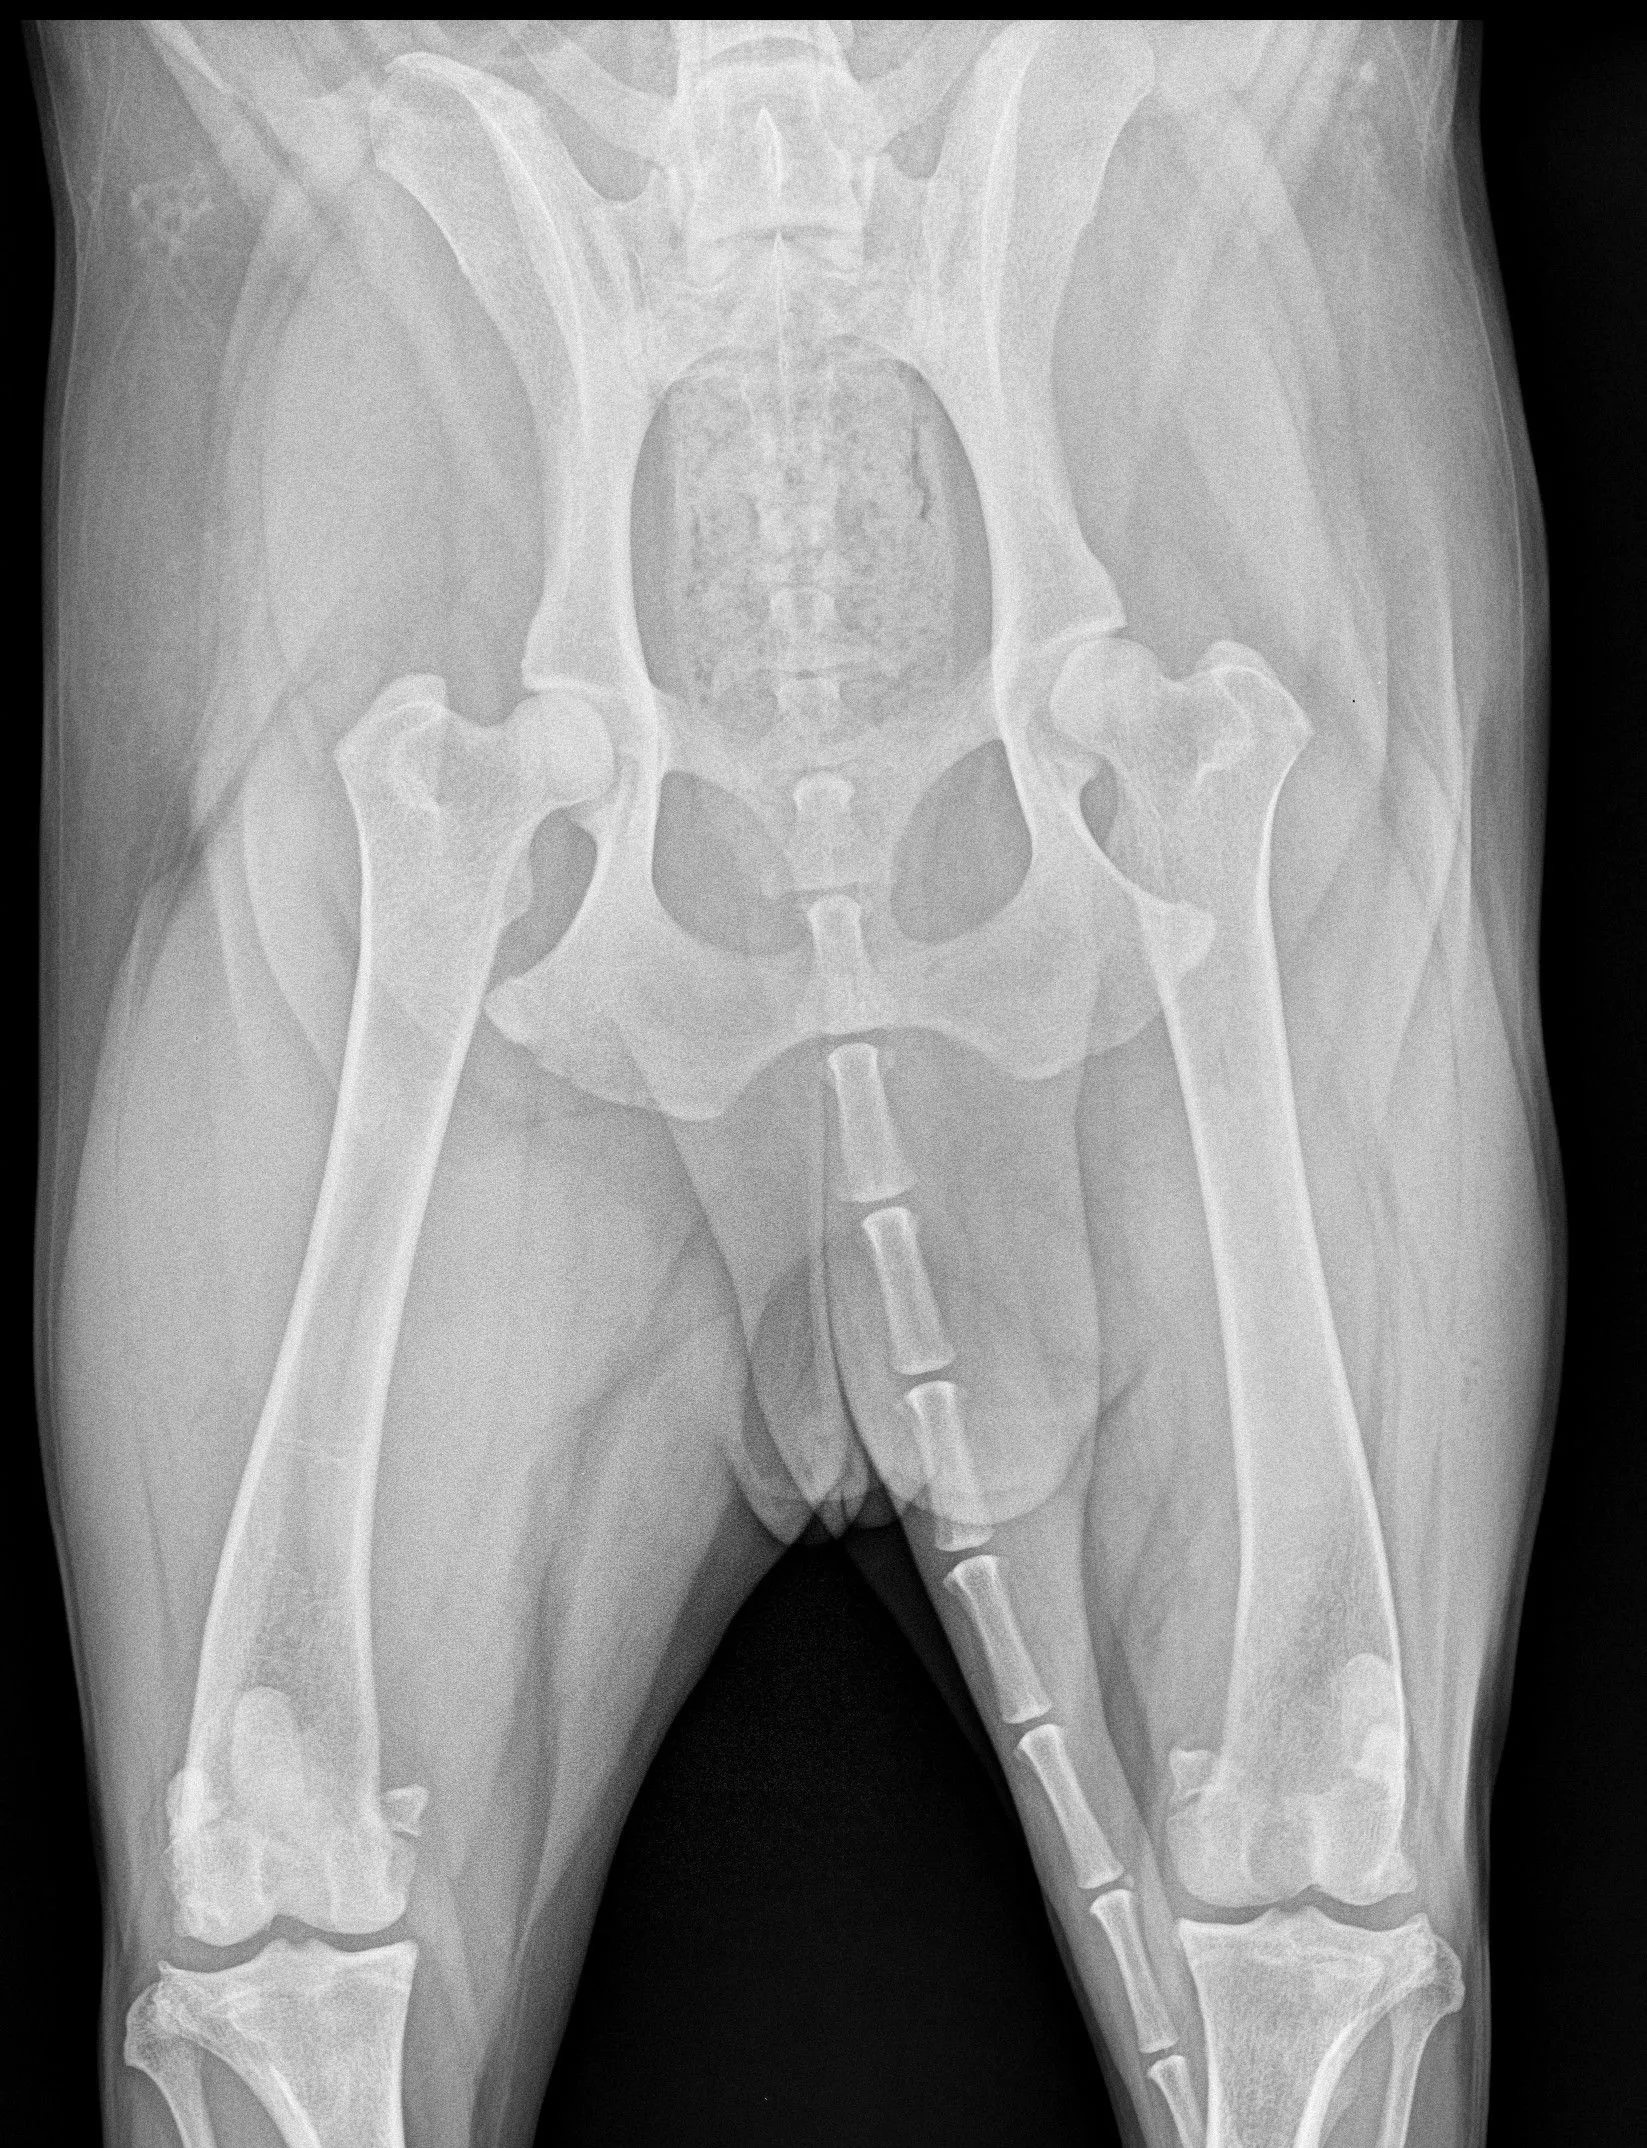

We have an in house digital x-ray so we can get your pet’s diagnosis and treatment plan started as soon as possible.